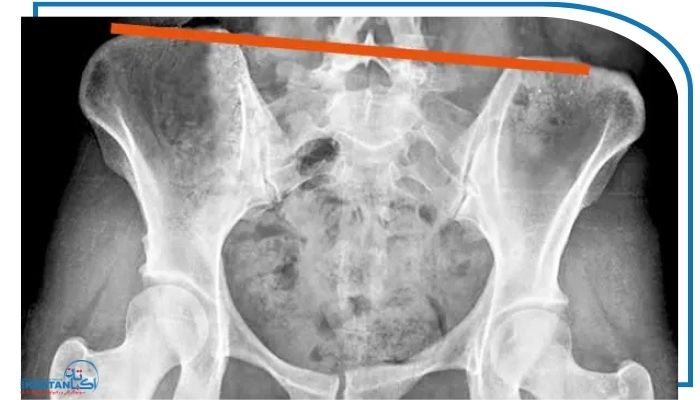

تصویربرداری پزشکی

در مواردی که ناهنجاری شدید است یا تشخیص دقیق لازم باشد از روش‌های تصویربرداری استفاده می‌شود:

عکس رادیولوژی: برای مشاهده‌ی موقعیت استخوان‌های پلویس، تقارن آن‌ها و بررسی هم‌زمان عکس انحراف ستون فقرات جهت ارزیابی ارتباط بین جابه‌جایی پلویک و اسکولیوز.